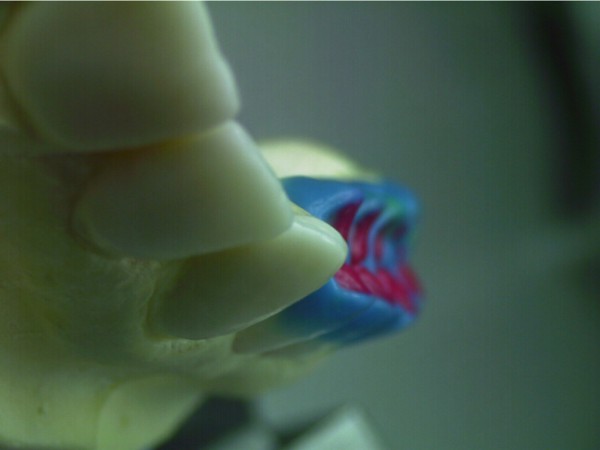

Entidades patológicas como el bruxismo, limitan la terapéutica odontológica y las certezas de un pronóstico favorable y prolongado en el tiempo. El strees, factor predisponente, y alteraciones morfológicas en la oclusión que impiden la disclusión de los sectores posteriores durante las excursiones de la dinámica mandibular, o factores desencadenantes. Caso Clínico Mujer , 53 años, derivado por especialista en Cirugía Máxilo Facial, con evidentes signos de hipertrofia de ambos maseteros. Clínicamente la carencia de las puntas caninas de ambos lados de ambas arcadas, nos habla de ciclos masticatorios eminentemente horizontales, tipo rumiante, donde el fenómeno de DOBLE DESGASTE de las cúspides estampadoras se pone en clara evidencia.(Fig.3 y 4 ) Ambos fenómenos(desgaste exagerado y extrusión dentaria nos habla de una invasión del espacio del maxilar superior, mediante la elevación del inferior, con las lógicas consecuencias musculares por acortamiento: Hipertrofia, acúmulo de ácido láctico, sobrecarga de los elementos tendinosos y capsulares, etc. Se le hace saber al paciente acerca de la necesidad de múltiples técnicas de Rehabilitación ANTES de llegar a reponer sus piezas perdidas. Se le pone en conocimiento de la necesidad de reponer SOLO hasta su primer molar, el que se reemplazará mediante una PREMOLARIZACIÓN, dado que el ancho de su cresta no permite reemplazar un primer molar salvo con riesgos de invadir el ESPACIO BIOLÓGICO necesario para un buen desarrollo de sus funciones. Es necesario tener en cuenta, que la pérdida de dimensión vertical por excesivo desgaste de la porción coronaria es siempre acompañada, por un descenso de las estructuras corticales, desfavoreciendo la relación CORONO/RADICULAR, lo que hace fundamental el ejercicio de unas fuerzas oclusales VERTICALES, a fin de no aumentar la movilidad de las piezas, una vez que la altura adecuada haya sido restablecida, verticalidad que solo se alcanzará mediante la implementación de una GUÍA ANTERIOR adecuada. Se estudia el caso clínicamente y se toman modelos de estudio debidamente montados en articulador semi ajustable en posición de ORC que es la única posición posible para rehabilitar, sin incurrir en alteraciones posicionales de la ATM, ni de elongaciones musculares y tendinosas que generen una nueva situación de strees muscular y empujen al sistema al bruxismo. Se analizan los modelos en forma estática y dinámica, donde se observan no solo las facetas parafuncionales de desgaste sino también la carencia de disclusión canina, patología generadora de dichas facetas, y que, Se confecciona un Encerado de Diagnóstico(Fig.A/B) a partir del cual se tallan las piezas en los modelos y se reproduce un juego completo de provisionales a utilizar durante el procedimiento clínico. (fig. 9) Se realizan las endodoncias y se refuerzan con Pernos Muñones Colados en oro, mediante los conceptos de Alineación Tridimensional correspondientes, instalándose los provisionales efectuados a partir del encerado de diagnóstico, los que cumplen con la tarea de discluir los sectores posteriores , tal como se concibió en dicho encerado.(Fig.10-11-12-13-14) Transcurridos seis meses de control, donde se verifican las funciones del sistema, dentro de un marco adecuado de ortofunción en el cual tal vez el más importante índice es el escaso desgaste de los provisorios, los que funcionan en una adecuada OCLUSIÓN en RELACIÓN CÉNTRICA y DIMENSIÓN VERTICAL ,situación esta apoyada por la presencia nocturna de una férula de Relajación, donde podemos observar y además «escuchar» al enfermo decirnos de su mejoría masticatoria y de la desaparición del «estado de agarrotamiento» que sentía en la boca al despertar, verificando que se siguen produciendo las disclusiones adecuadas en todas las excursiones mandibulares. Realizamos entonces al estudio radiológico adecuado, procediendo a instalar ocho(8) implantes roscados, tres de los cuales son insertados con una ligera elevación de ambas mucosas sinusales intra alveolarmente.(Fig.15-16-17) Transcurridos tres meses más y verificando la correcta cicatrización tomamos impresiones para realizar los abuttments de oro correspondientes, sobre los que instalamos un nuevo juego de provisionales que ya dan carga a los implantes.(Fig.18-19-20-21-22) Ahora estamos en presencia de un Sistema Estomatognático que presenta las características idoneas para funcionar, características estas que observamos permanentemente sobre todo la función de la GUIA ANTERIOR. Recién entonces confeccionamos las Restauraciones Periféricas Totales, las que serán realizadas en Porcelana sobre Oro . Se procede entonces a la confección de los sectores posteriores constituidos en este caso por tres premolares en cada hemiarcada de cada maxilar.(Fig.29-30) Se constatan la Estética, el Ajuste Cavo Superficial, El Espacio Libre Interoclusal, la Dinámica Mandibular,etc.(31-32-33-34-35-36-37-38-39-40) Evidentemente un caso exitoso no muestra las bondades de un método. Sin embargo, la casuística popular acerca de la imposibilidad de ser implantados aquellos pacientes que padecen bruxismo es tan frecuente como realizar en bruxómanos, coronas totales con oclusal metálica a fin de no permitir que las fuerzas de la oclusión destruyan nuestro «trabajo, sin tener en cuenta que no es la dureza del metal quien evita la destrucción…. BIBLIOGRAFÍA: 1-Oclusión y Diagnóstico en Rehabilitación Oral. 2-Disfunción temporo Mandibular y Equilibración Oclusal. 3-Rehabilitacion Bucal. 4-Problemas Oclusales. 5-Oclusión. 6-Oclusión. Conceptos para el Clínico. 7-Disfunción temporo Mandibular. 8-Neurofisiología de la Oclusión. 9-Gnatología.Principios y Conceptos.José dos Santos. 10-Oclusión y Rehabilitación. 11-Procedimientos Clínicos y de Laboratorio de la Oclusión Orgánica.